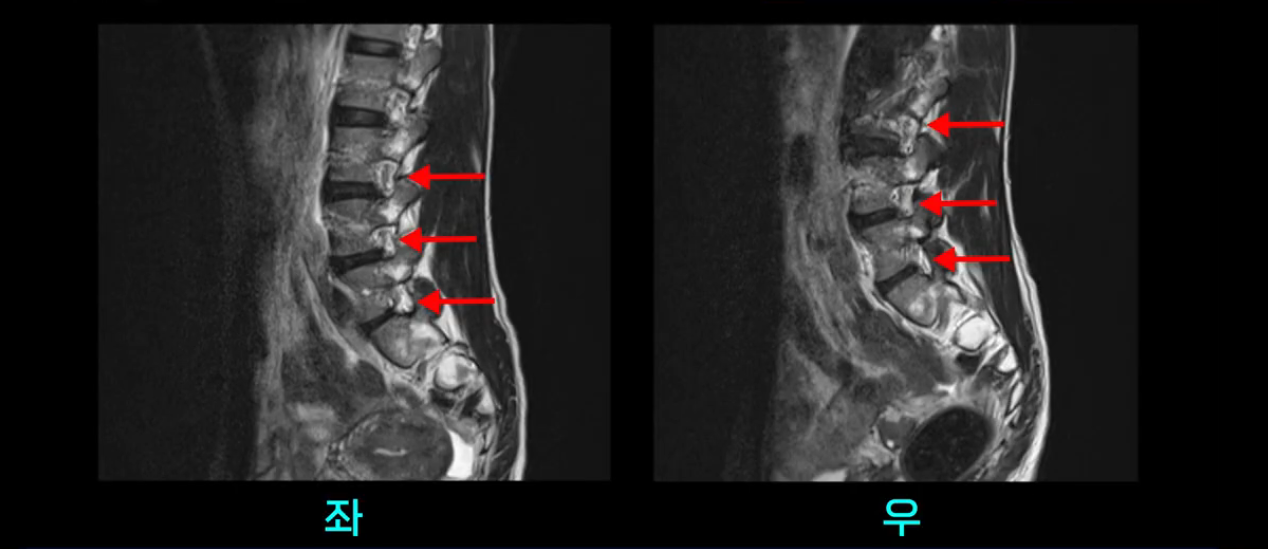

이분 MRI를 보시면 두 마디의 퇴행성디스크가 있습니다. 그리고 디스크가 조금씩 밀려 나와 있고요. 그런데 디스크 탈출 정도는 두 마디 다 심하지 않습니다. 4번 5번에는 디스크 탈출이 약간 있고,

척추관협착도 약간 진행이 되고 있고요.

5번 1번은 디스크 탈출이 가운데 쪽으로 살짝 있습니다.

또한 양쪽 신경 가지가 빠져나가는 추간공은 매우 넓은 상태입니다.

중요한 것은 이 정도 경미한 탈출과 협착으로는 양쪽 다리가 저리고 아플 수가 없습니다.

이분 MRI를 보시면 퇴행성디스크가 있고 약간의 협착이 있지만 이 정도의 퇴행성디스크와 협착으로는 신경이 눌려서 양쪽 다리가 저리고 아픈 증상이 나올 수가 없습니다. 그래서 MRI와 이 환자분의 다리 증상이 매치가 안 된다고 하는 의사들이 많은 겁니다.